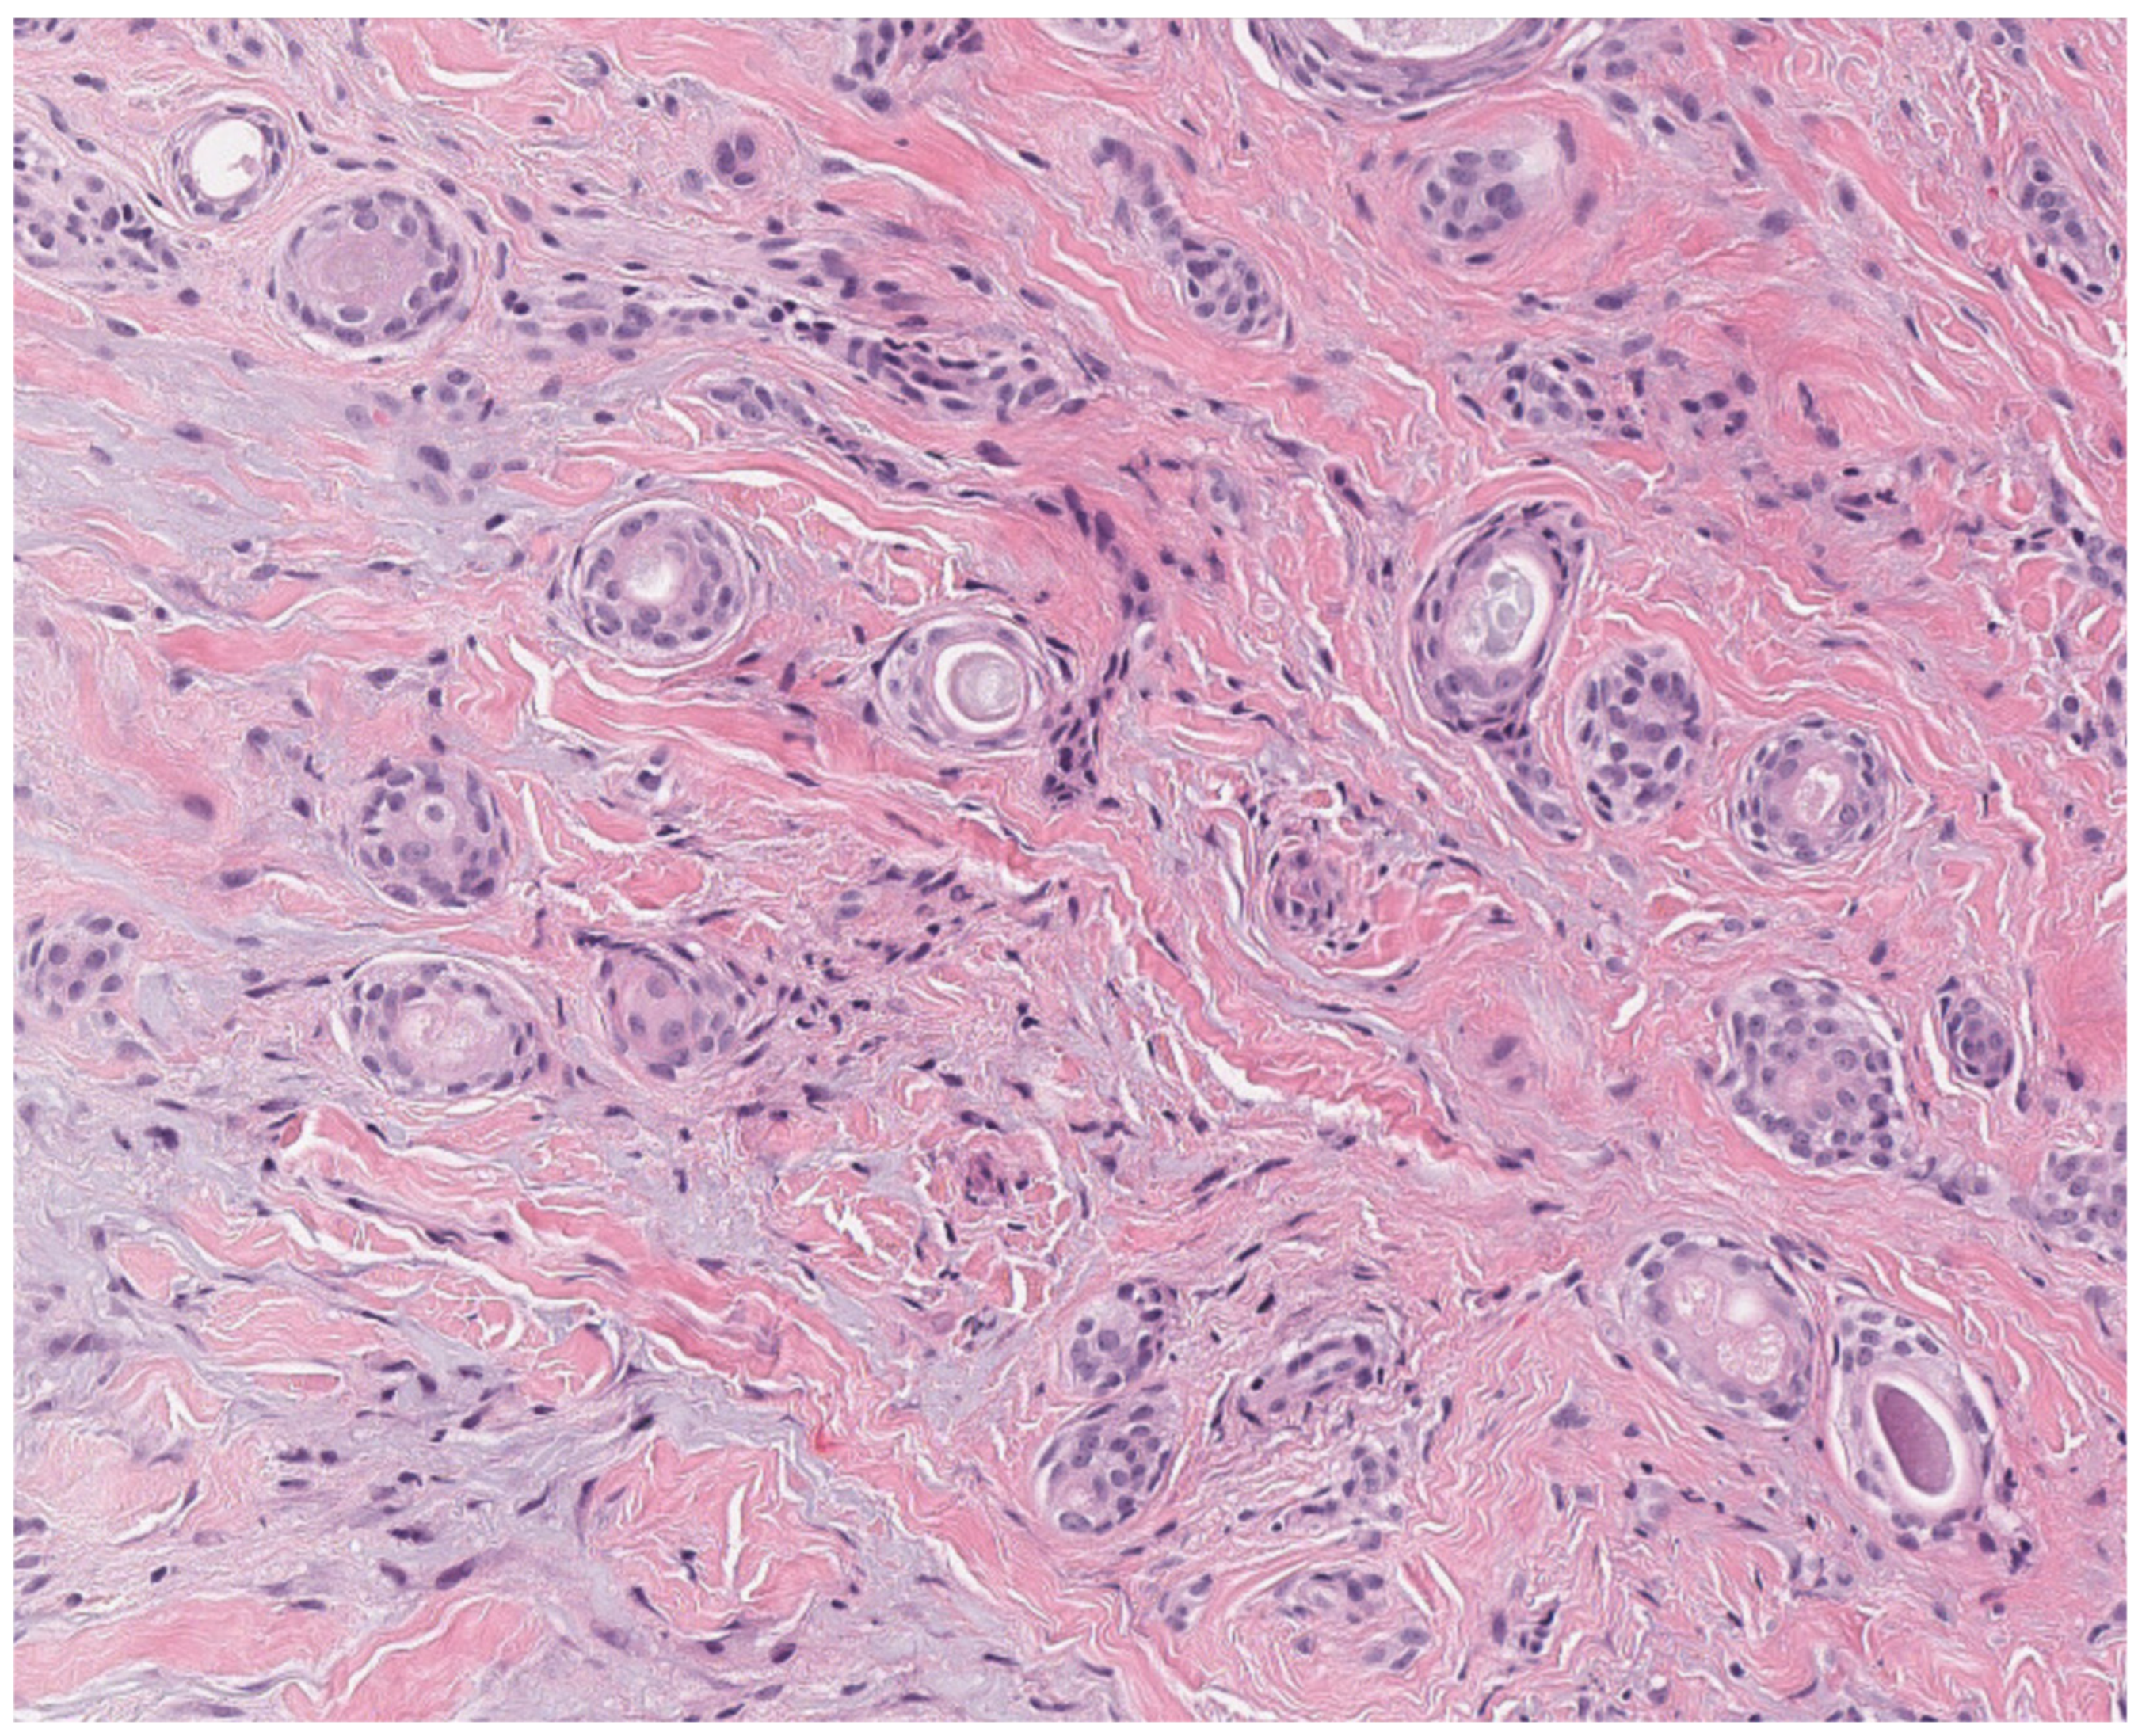

2.2. Tricholemmoma

- Gustafson, S.; Zbuk, K.M.; Scacheri, C.; Eng, C. Cowden syndrome. Semin. Oncol. 2007, 34, 428–434. [Google Scholar] [CrossRef]

- Kaptan, M.A.; Kattampallil, J.; Rosendahl, C. Trichilemmoma in continuity with pigmented basal cell carcinoma; with dermatoscopy and dermatopathology. Dermatol. Pract. Concept. 2015, 5, 57–59. [Google Scholar] [CrossRef]

- Tardío, J.C. CD34-reactive tumors of the skin. An updated review of an ever-growing list of lesions. J. Cutan. Pathol. 2009, 36, 89–102. [Google Scholar] [CrossRef]

- Romano, C.; Schepis, C. PTEN gene: A model for genetic diseases in dermatology. Sci. World J. 2012, 2012, 252457. [Google Scholar] [CrossRef]

- Al-Zaid, T.; Ditelberg, J.S.; Prieto, V.G.; Lev, D.; Luthra, R.; Davies, M.A.; Diwan, A.H.; Wang, W.; Lazar, A.J. Trichilemmomas show loss of PTEN in Cowden syndrome but only rarely in sporadic tumors. J. Cutan. Pathol. 2012, 39, 493–499. [Google Scholar] [CrossRef] [PubMed]

- Hobert, J.A.; Eng, C. PTEN hamartoma tumor syndrome: An overview. Genet. Med. 2009, 11, 687–694. [Google Scholar] [CrossRef] [PubMed]